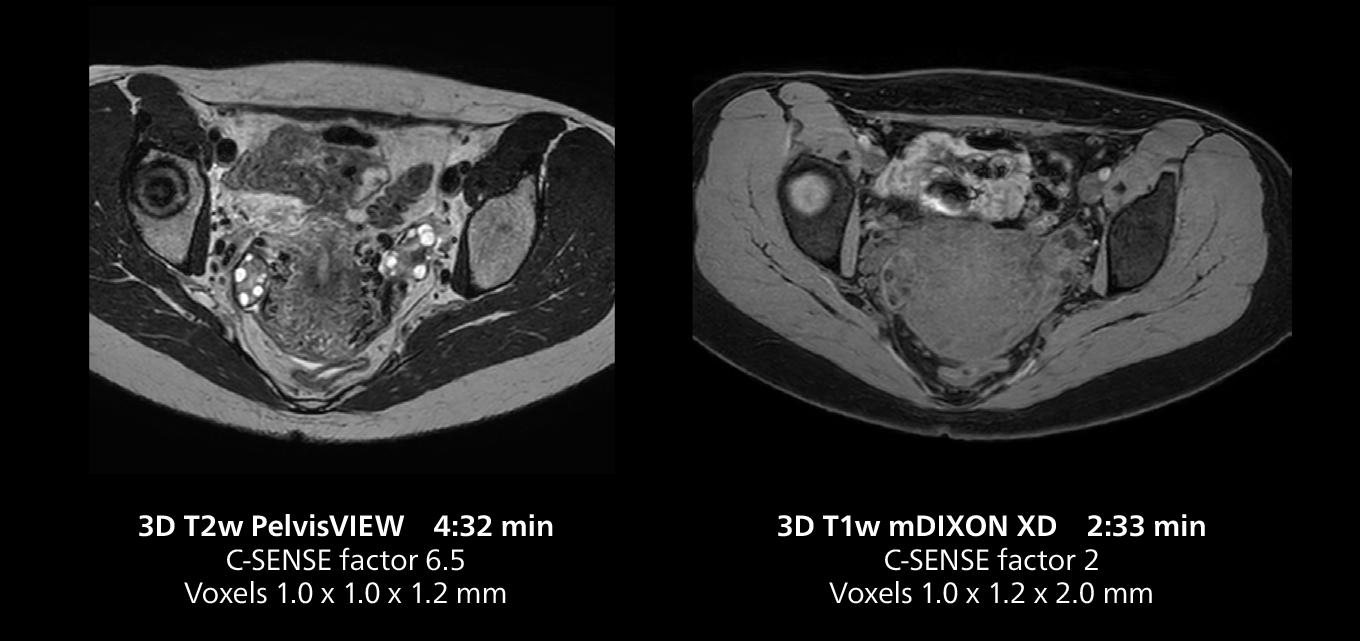

The isotropic high resolution 3D sequence in this MRI case allows for reformatting to obtain other orientations with high quality. Acquired on the MR 5300 system.

Dr. Gellée highlights the robust free-breathing scans as “the feature that makes the biggest difference in my daily work. The 3D free breathing sequences are very reproducible, and the axial acquisition is very good. For example, in endometriosis, which is one of my focus areas, it provides high contrast and good resolution so that I can see small details. We also use free breathing for liver and pancreas imaging. In multi-phase liver studies, 4D Free Breathing delivers 3-second temporal resolution, making a dynamic scan with more than one arterial phase possible.”

The MR 5300 with Compressed SENSE is up to 50%** faster for many exams. It can provide routine exams in less than 5 minutes and whole-body exams in less than 20 minutes. Saint-Augustin has taken advantage of that speed to create highly efficient protocols. The hospital’s standard stroke protocol is just about 8 minutes, and standard ENT, prostate PIRADS staging, and endometriosis studies all clock in at just about 10 minutes.***

“We have more speed in 3D sequences,” Dr. Gellée states. “With Compressed SENSE, we can replace two or three 2D scans withone high-quality 3D scan. High quality additional orientations are then obtained by post-processing of the 3D data set, thus saving scanning time.”